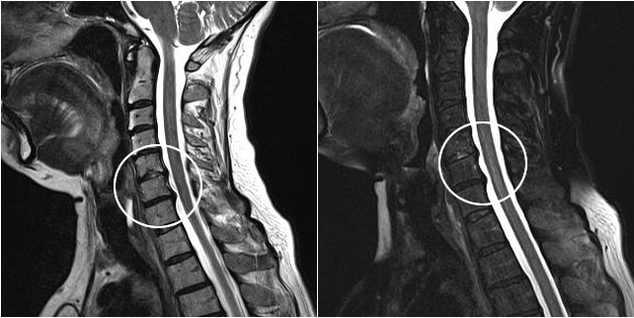

Diagnostiko-metodo modernoen artean, MRI eta CT daude, kartilagoaren eta hezur-ehunaren suntsipen-prozesuak zehatzen aztertzea ahalbidetzen dutenak. Gainera, teknika hau erabiliz, gaixotasunaren iturritik gertu herniak eta beste ehun bigunen akatsak diagnostikatzea komeni da.